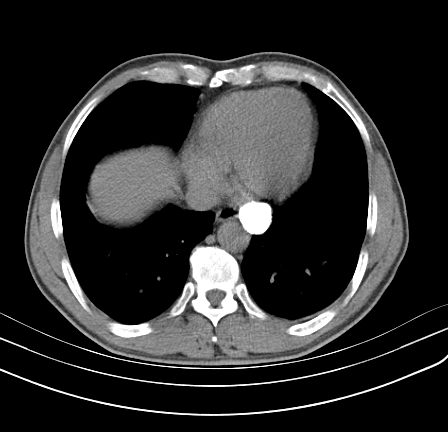

以下是引用影像孺子牛在2009-5-20 23:18:00的发言:[br]左侧后心膈角处类椭圆形钙化灶,最常见的是淋巴结钙化,但太大了不支持,其它如食管囊肿钙化、实性畸胆瘤等。何东西钙化真不好定。

以下是引用zbp537在2009-5-20 20:52:00的发言:[br]钙化灶,来源不好说。